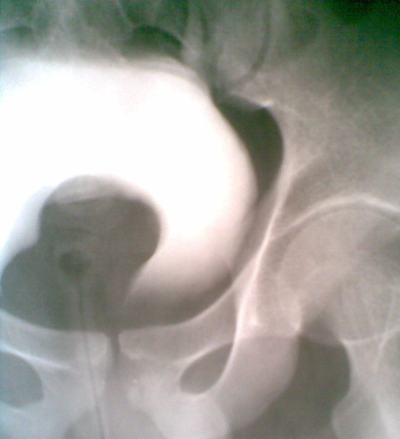

Kết quả siêu âm niệu qua thành bụng: thận phải có kích thước 6x8cm, thận trái bình thường. Tại cổ bàng quang có khối bề mặt nhắn, kích thước 6x5cm.

Kết quả UIV cho thấy trên phim 15 đến 180 phút thận trái bình thường (đường bài niệu giãn nhẹ do ép bóng tại niệu quản đoạn dưới), thận phải không ngấm thuốc cản quang. Bàng quang có khối choán chỗ (xin xem hình).